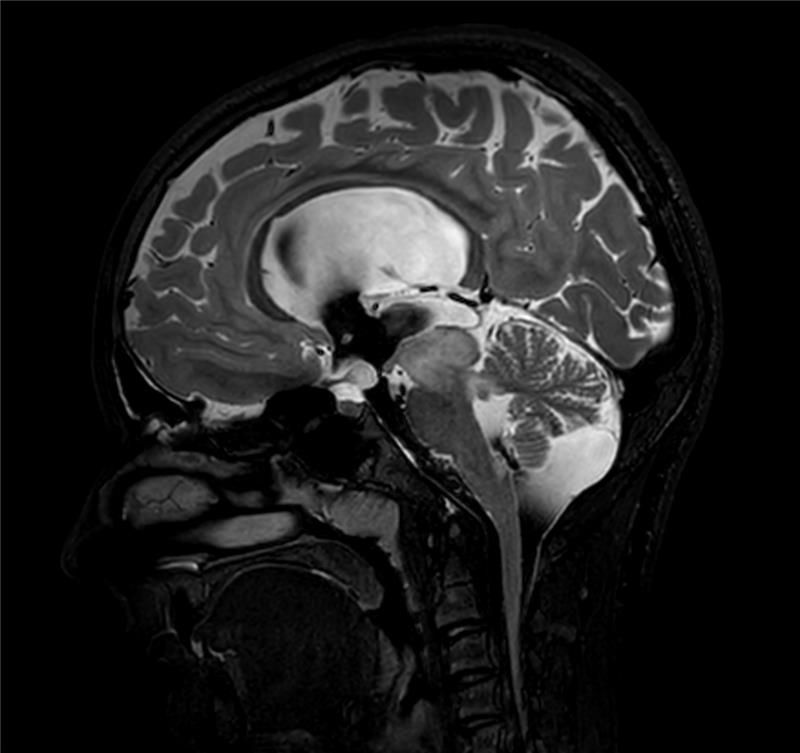

Sagittal 3D T1w TFE